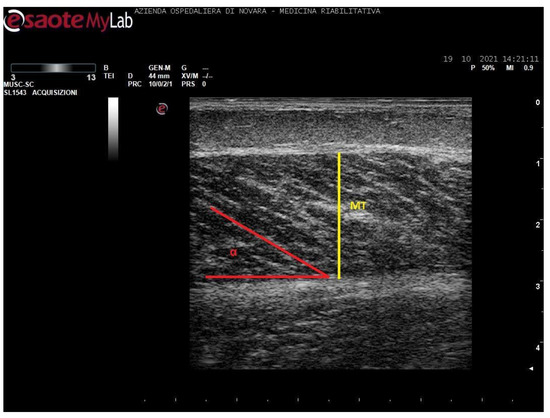

We acquired images of the medial gastrocnemius (MG) and soleus (SOL). Images were processed through the software ImageJ (National Institutes of Health, USA) in order to measure the muscle thickness (MT, cm), the cross-sectional area (CSA, cm2), the pennation angle (α, °), and the mean gray value (MGV, range 0-255). MGV was assessed considering the whole muscle longitudinal section as region of interest (ROI). The gray scale spreads from 0 (black) to 255 (white).

The subject was in sitting position, with hip and knee flexed at 90°, the ankle in neutral position, and the feet leaning on a hard surface parallel to the sitting plane. For MG, the probe was placed at the junction between proximal and intermediary third of the calf in correspondence of the maximal CSA of the muscle. For SOL, the probe was placed in order to visualize the medial gastrocnemius myotendinous junction on the upper-left corner of the screen in longitudinal position.

Measurements were taken as shown in Figure 1, Figure 2, Figure 3 and Figure 4.

Figure 4. Ultrasound image of soleus in longitudinal section. In yellow: muscle thickness (MT), in red: pennation angle (α), *: myotendinous junction of medial gastrocnemius.